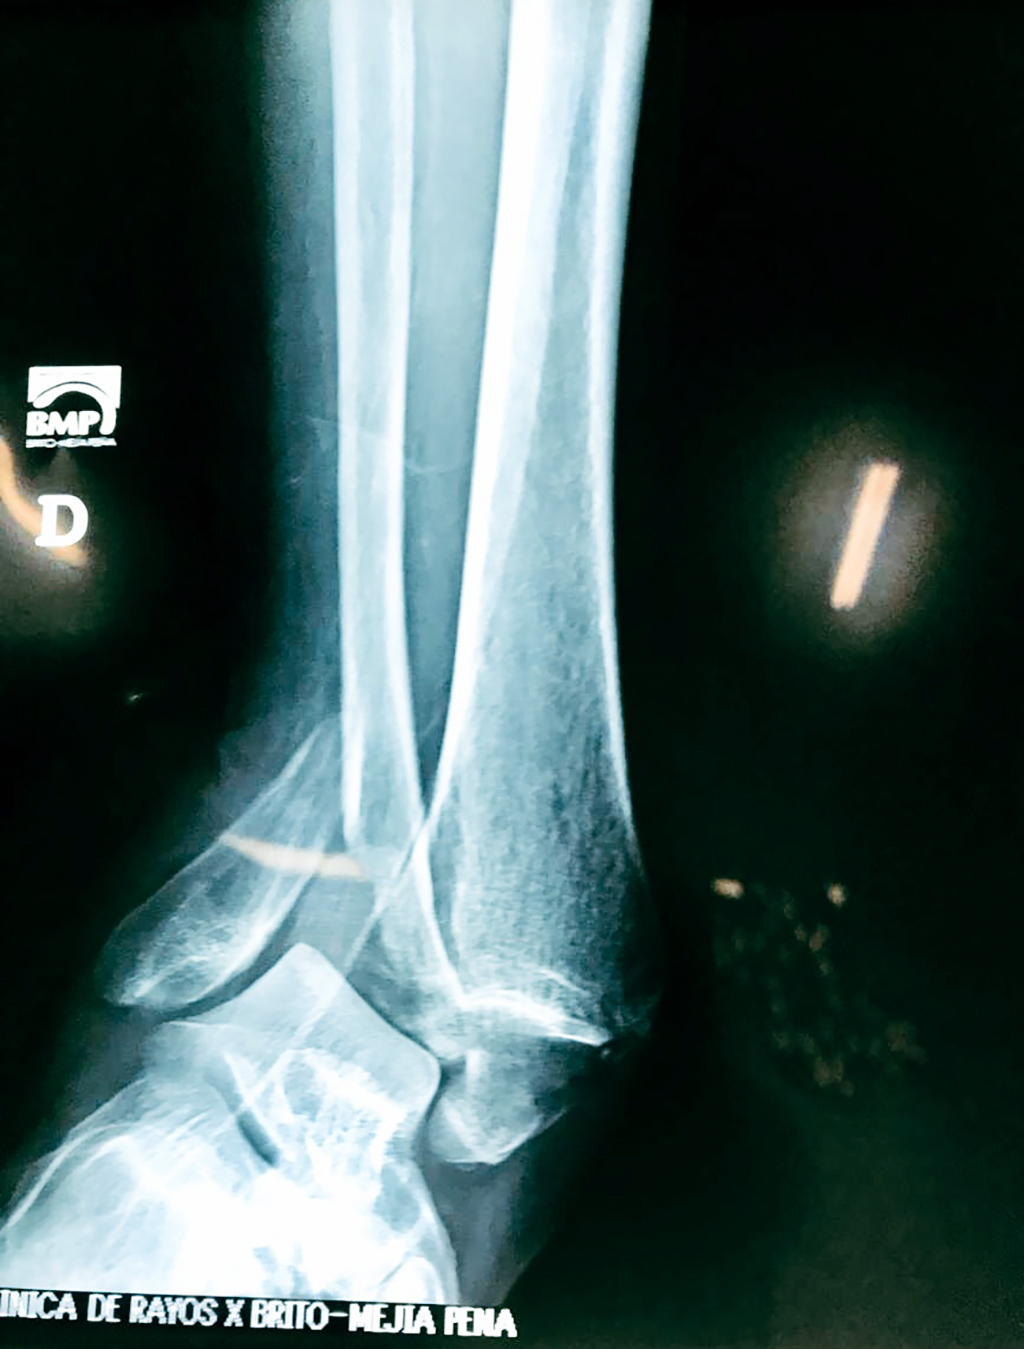

Algunas fracturas de tobillo pueden requerir cirugía si:

- Los extremos de los huesos están desalineados entre sí (desplazados).

- La fractura se extiende hasta la articulación del tobillo (fractura intra-articular).

- Los tendones o ligamentos (tejidos que sujetan los músculos y los huesos entre sí) están rotos.

- El médico cree que sus huesos probablemente no sanen apropiadamente sin cirugía.

- El médico considera que la cirugía puede permitirle una recuperación más rápida y confiable.

- En los niños, la fractura involucra la parte del hueso del tobillo donde el hueso está creciendo.